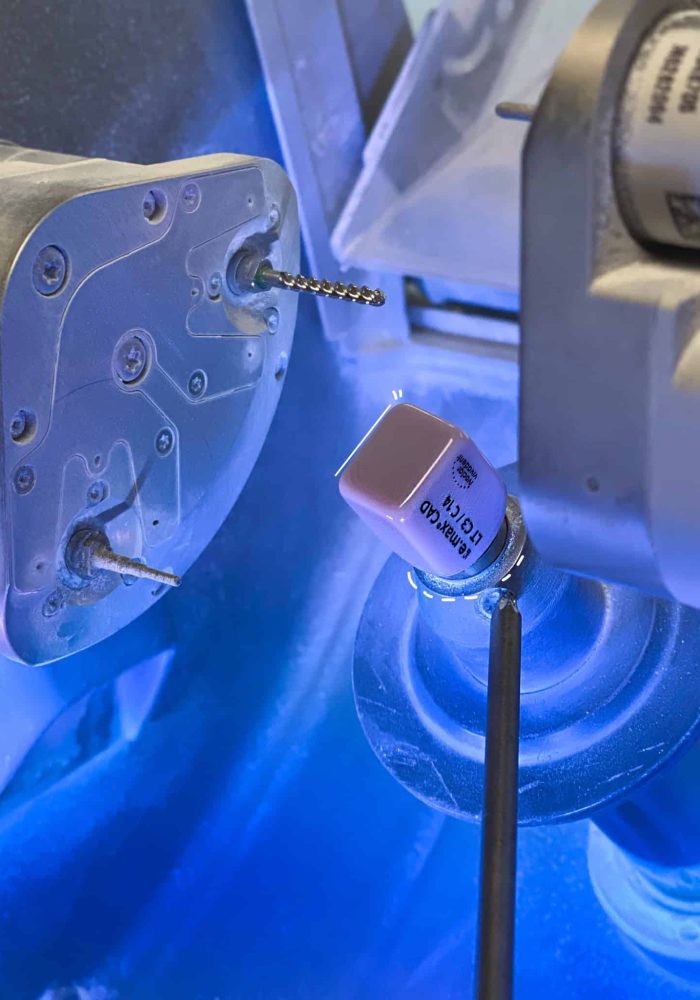

Restorative DentistryRestorative Dentistry